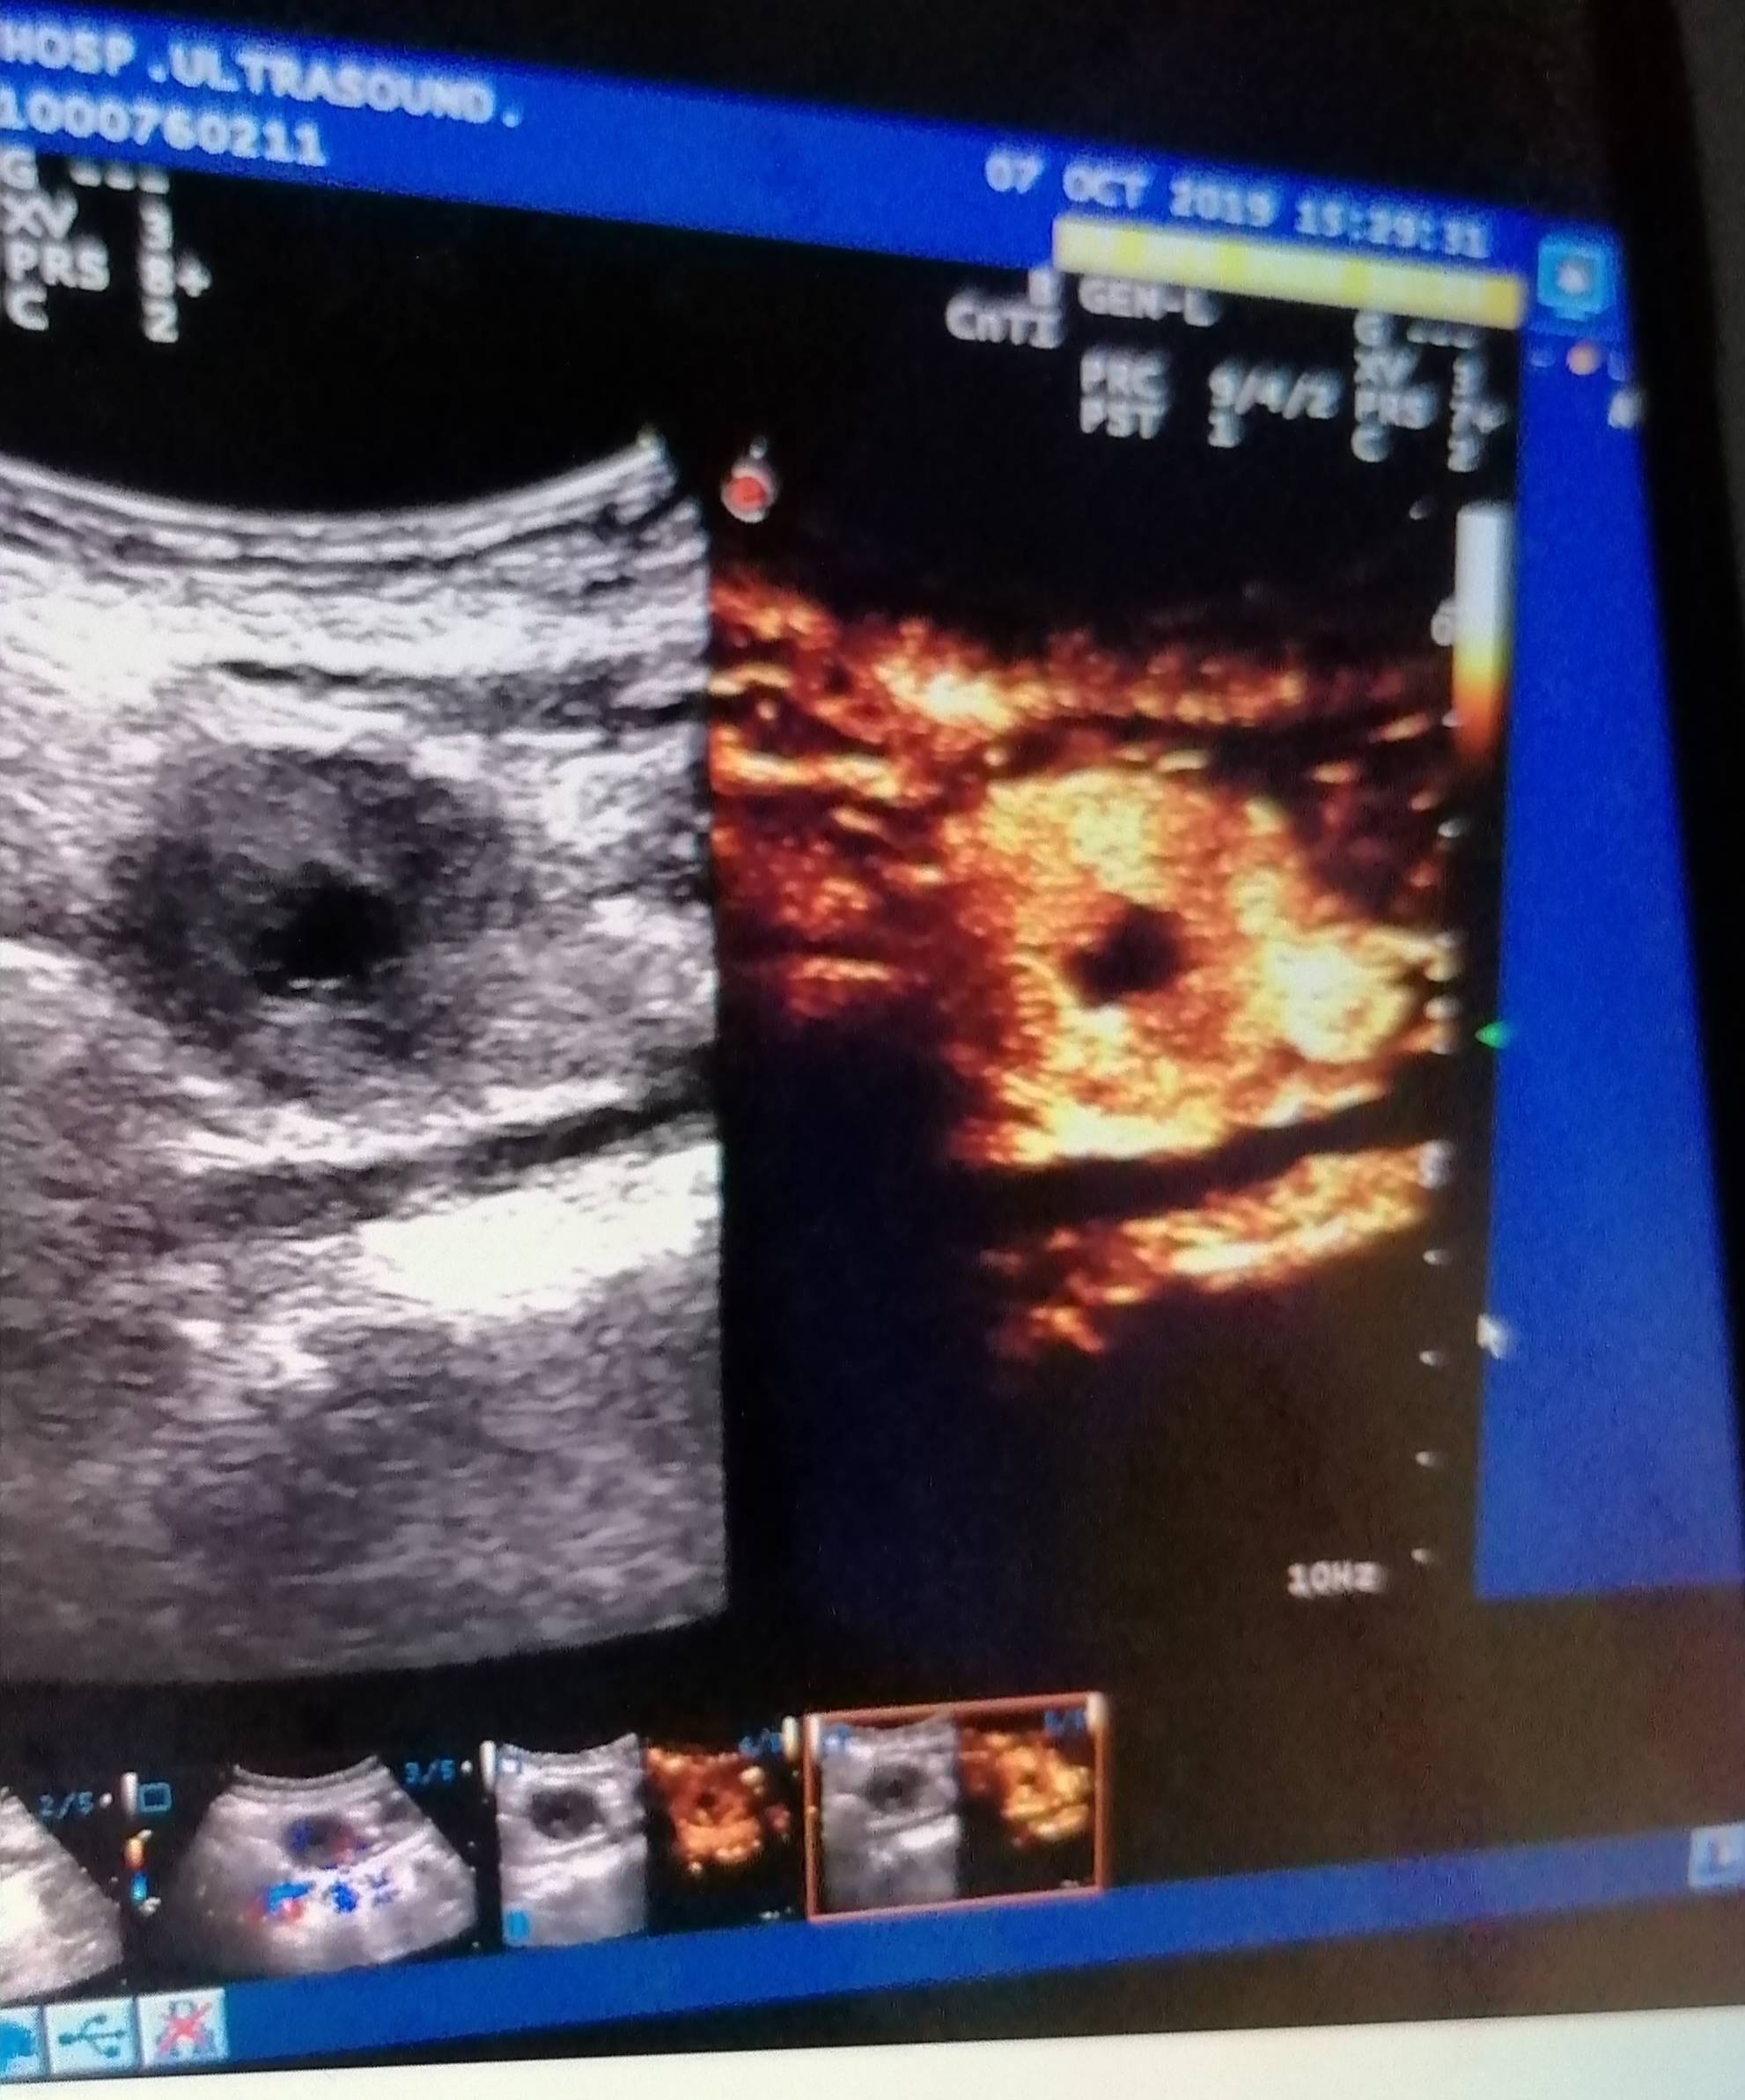

十年前,我被诊断出患有胃癌,那一刻,我仿佛跌入了无尽的深渊,生活失去了往日的色彩。然而,我没有选择放弃,在医生的精心治疗下,我勇敢地接受了手术,开始了漫长的抗癌之路。手术后的日子,充满了痛苦与挑战,每一次化疗,都像是一场生与死的较量,但我都咬牙坚持了下来。

然而,命运似乎并没有就此放过我,手术的三个月后,再一次复发,癌细胞转移至腹膜后,我又一次被推上了风口浪尖上。面对这样的打击,我也曾感到绝望和无助,但想到家人和朋友们的关心与支持,我告诉自己不能放弃,于是,我再次鼓起勇气,与病魔展开了新一轮的较量。

如今,我已经走过了近十年的抗癌之路,虽然身体依然带着肿瘤,但我依然积极乐观地面对生活。我深知,人生就像一场行路,总会有风风雨雨,但也会有美丽的风景,在这场旅程中,我学会了珍惜每一个当下,感恩身边的每一个人。